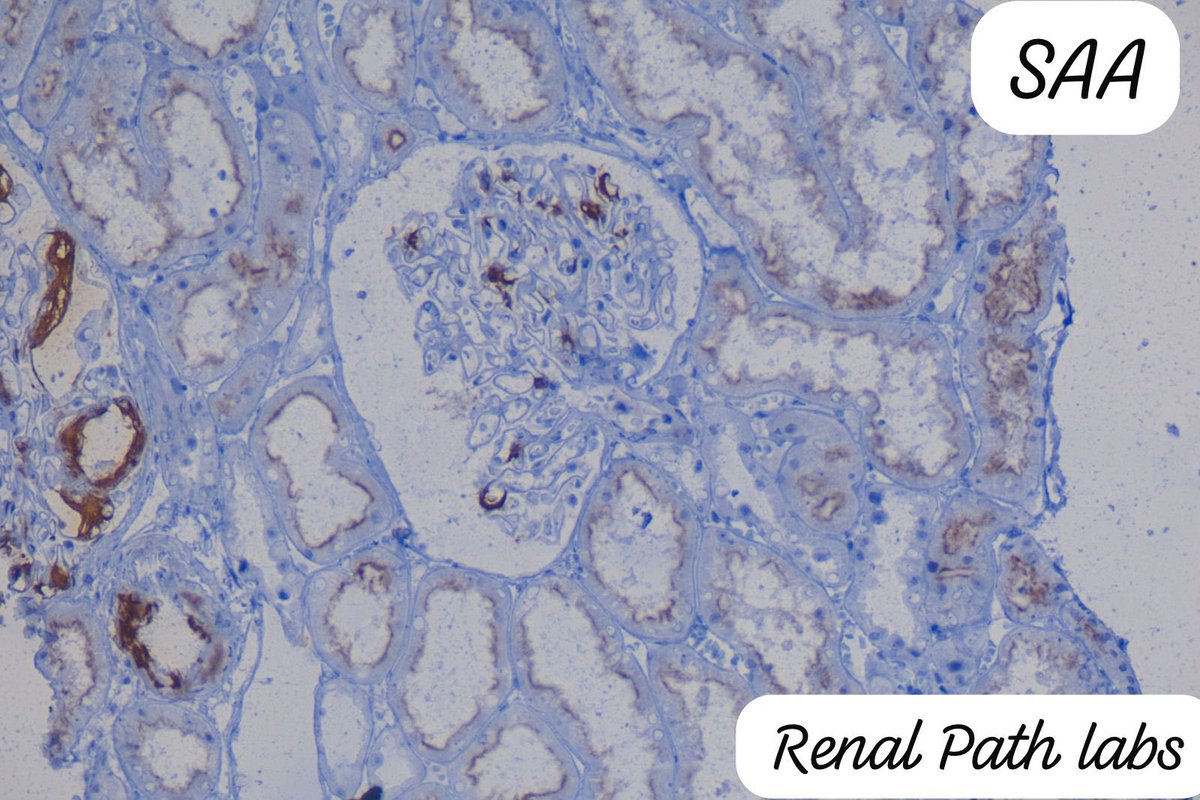

An Ask Renal question for the #NephTwitter #NephX by - @RenalPathLabs ๐Ÿ‘‡ https://t.co/6rtoQHJnaD

@RenalPathLabs

Renal Path Labs

1 year

On demand of our Pathology and Nephrology residents, we will try to simplify Renal Pathology through our images.. How the amyloid looks like in different stains! #Amyloid #RenalPathology #AskRenal #PathTwitter #Nephtwitter

An Ask Renal question for the #NephTwitter #NephX by - @RenalPathLabs ๐Ÿ‘‡ https://t.co/lYlES08GKZ

5 cases of amyloid in 2 days r too much for a small vol. kidney bx centre. Age-20to 68. 4: SAA+, 1:light chain restricted.Beware.This innocent material is causing much harm! It can be subtle as in our previous post. #RenalPath #AskRenal #Nephtwitter #RenalPathSociety #Pathtwitter